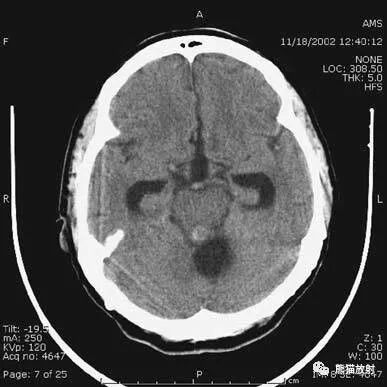

钩回疝:

是当代偿机制不能适应占位性病变时的结果。

基底节区大量高血压性脑出血,破入脑室及蛛网膜下腔,周围水肿,脑干周围空间消失;脑干出血、脑积水。